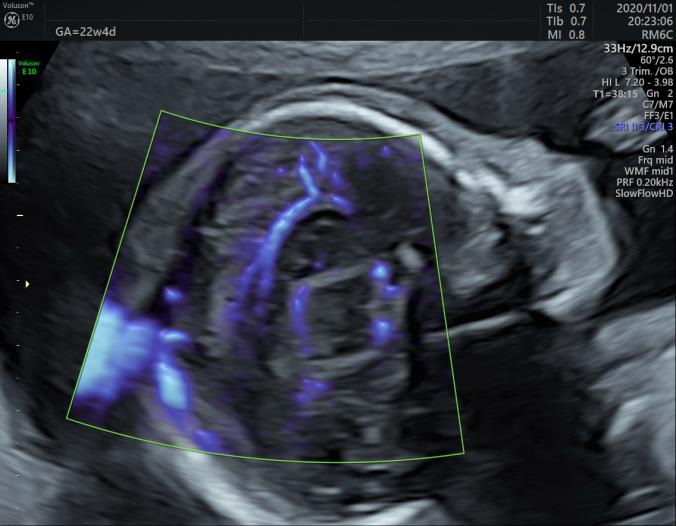

煊流成像技术:SlowflowHD:快速、直观显示微小血管

胼胝体周动脉超低速血流灌注状态

Radiantflow:更少的频闪和增强的血管边界显示

一台专业优秀的妇产超声机,对于产前胎儿四维超声筛查、子宫双侧附件及女性盆底功能障碍性疾病检查需要具备高端专业的处理机制。GE Voluson E10 BT20金标版在原有高端平台的基础上搭载了全新的煊光成像平台、煊影成像技术和煊流成像技术,能够360°高清立体、超真动态地显示宝宝的实时活动图像,创新性的二维立体血流成像模式Radiant flow、超低速血流成像模式 SlowflowHD即便是微小的血管也能轻松的快速显现,提高了血流的视觉敏感性,卓越的图像质量,大大提高了临床诊断的准确率。